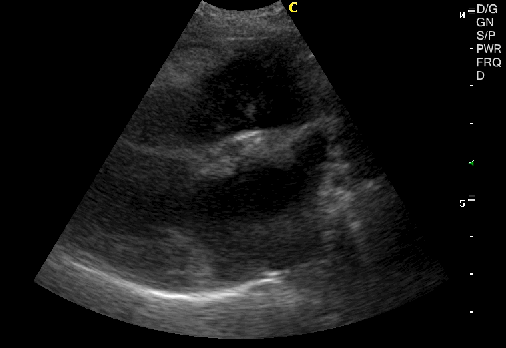

Patient: 11 year old female spayed Beagle.

History: The owner complained about coughing and exercise intolerance.

Findings:

- Large, mixed echotexture mass that originated from the base of the heart, between the two large vessels (Pulmonary artery and Aorta), protruding into the right atrium.

- Pericardial effusion.

- Mild mitral valve degeneration with systolic regurgitation jet (1.5m/s)

- Mild dilated hepatic veins and caudal vena cava.

Diagnose: The owners didn’t want to proceed to further diagnostics. The patient went home with furosemide and ACEI. In literature has been described that almost all of the cardiac tumors originate from the right atrium1. The intrapericardial neoplasms with the highest frequency are Heamangiosarcomas (40.4%). There are also reports of Chemiodectomas2 (17.3%) and ectopic thyroid masses1 (<1%).